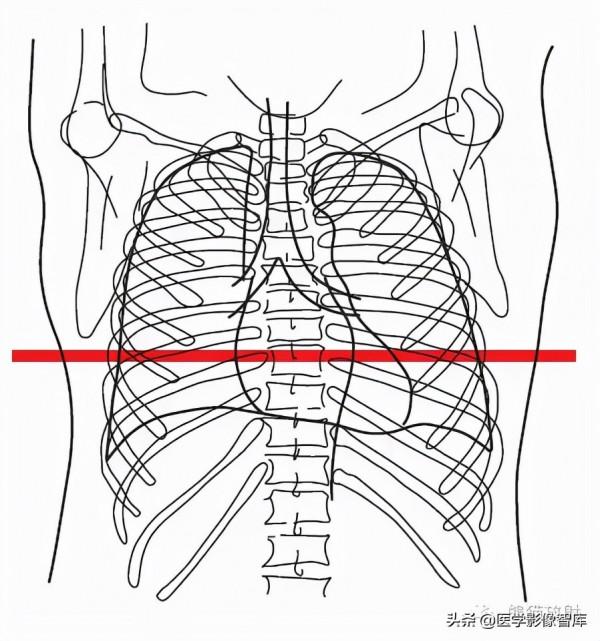

胸部